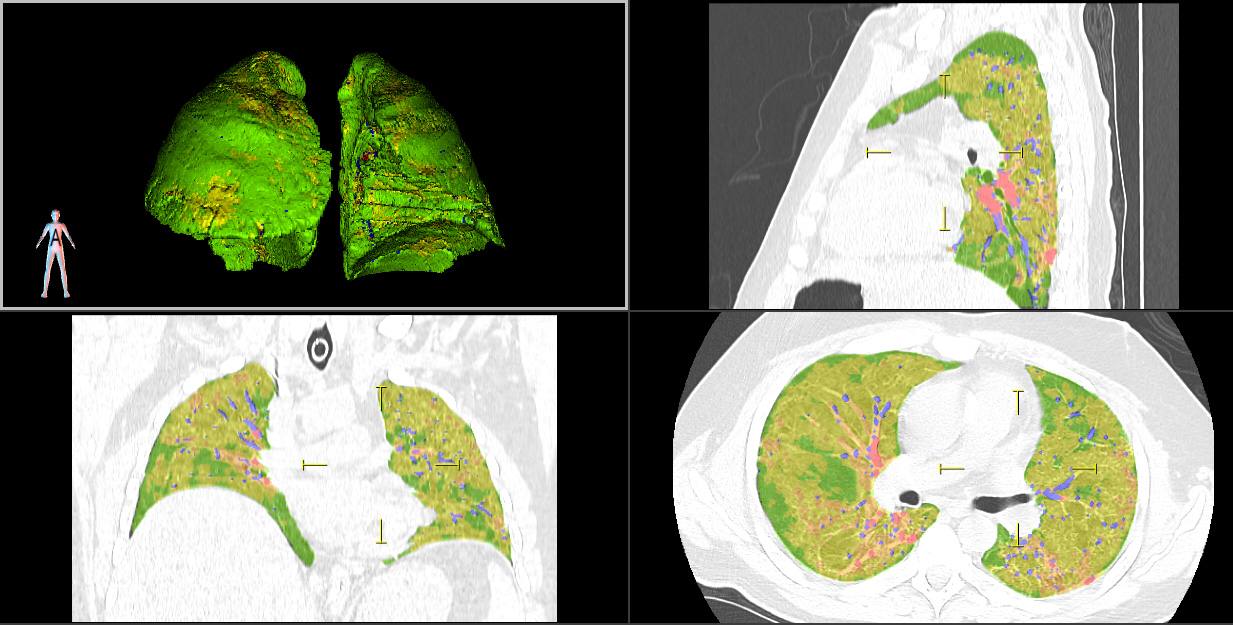

Программа по рентгеновским компьютерно-томографическим изображениям в автоматическом режиме выдаёт качественные и количественные данные о патологических областях органов дыхания, что является основой для принятия тактических и лечебных решений при ведении пациентов с коронавирусом.

Модуль успешно применяется в ряде медицинских учреждений Москвы, в том числе в 52-й городской клинической больнице. Там проводится его клиническое использование для прогнозирования динамики и исхода поражений легких, а также для проведения сравнительного анализа эффективности противовирусной терапии и респираторной поддержки.

Программа работает в составе АРМ врача-диагноста «Гамма Мультивокс Д2».